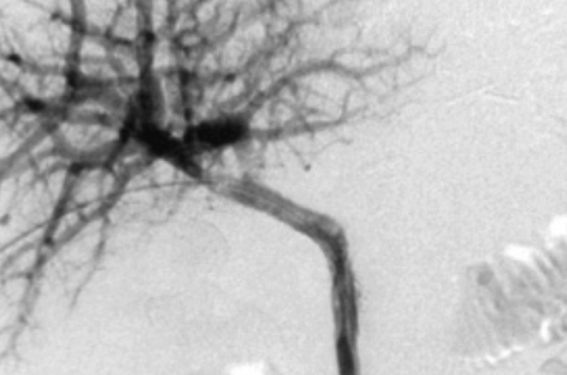

Stenting de sténoses portales tumorales malignes préocclusives ou occlusives : quels patients, quelle technique, pour quels résultats ?multidisciplinarité

L’hypertension veineuse portale (HTP) préhépatique peut être observée dans diverses affections, bénignes et malignes. Elle représente 5 à 10 % de tous les cas d’HTP(1). Elle est plus fréquente après une transplantation hépatique(2). D’autres causes bénignes incluent les maladies inflammatoires, telles que la pancréatite, les conditions thrombotiques, la sténose ou l’occlusion postchirurgicale et la radiothérapie. Elle est causée dans 15 à 24 % des cas par une tumeur maligne(1,2), qui est principalement une tumeur hépatobiliaire ou pancréatique et, dans certains cas, elle peut être le résultat d’une compression par des métastases ganglionnaires, en particulier de carcinomes gastrique ou mammaire(3).

L'HTP peut se manifester par un ou plusieurs des symptômes suivants : douleurs abdominales, ascite, thrombocytopénie associée à une splénomégalie, dysfonctionnement hépatique ou développement de varices péridigestives pouvant être hémorragiques (4). L’hypoperfusion portale intrahépatique peut...